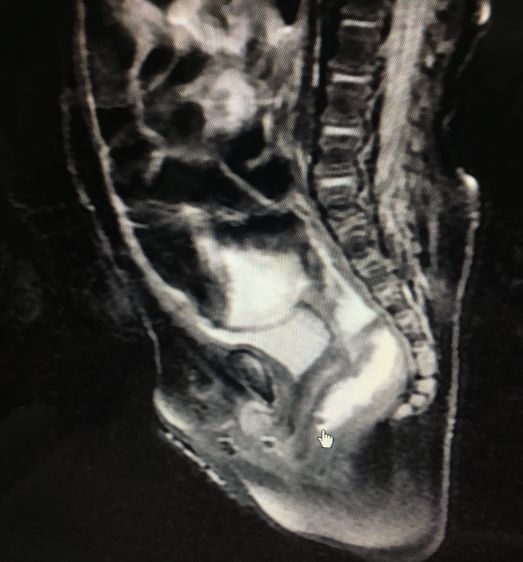

(片子显示:该男孩因无肛长期导致的巨结肠,足足20厘米 ,要切掉)